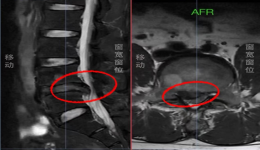

微创之光|茂医脊柱外科:以微小切口解决患者腰椎间盘突出大问题

“手术效果真好!今早起来发现腰腿不痛了,请问今天我可以起床活动了吗?”术后第二天早上查房时,34岁的杨先生激动地询问茂名市人民医院脊柱外科一区主任医师梁晓,兴奋之情溢于言表。据了解,杨先生被严重的腰椎间盘突出症困扰折磨了一年多,右腿...